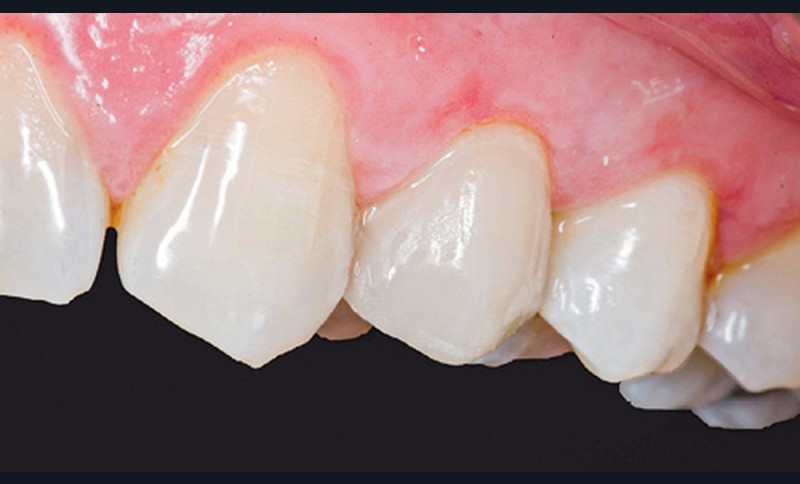

Après essayage, le veneerlay est conditionné, puis l’assemblage est réalisé à l’aide d’une colle universelle sous champ opératoire (fig. 15 et 16).